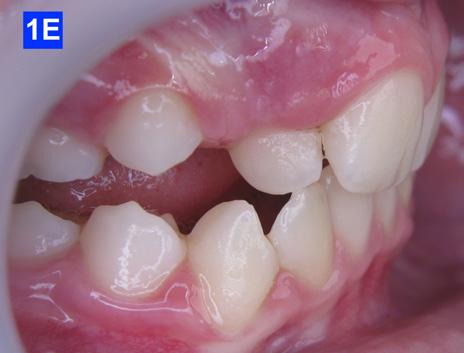

Clinical Micro-esthetic appraisal revealed Angle Class I molar relationship. The arches were narrow, there was crowding, and she had a posterior crossbite. The patient had 2.0 mm overjet and 1.5 mm overbite. There was an anterior cross bite on #12(7) and #22(10), which indicates Class III tendency. The lower airway was very narrow, only 5.0 mm; however, the patient denied SDB symptoms. She did, however, present with symptoms and signs of TMJ dysfunction (Figure 1-D, E, F, G, H,)

Figure 1E: Pre-treatment, right lateral view